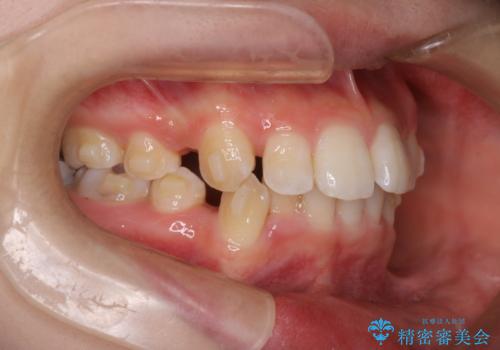

重度の歯のがたつきを、目立たない矯正と抜歯で根本改善

- 前歯から奥歯にかけて歯の重なりが激しい歯のがたつき(重度叢生)を主訴にご来院されました。精密検査の結果、歯が並ぶスペースが大幅に不足しており、歯並びを整え、口元を美しく引っ込めるためには、スペースの確保が必要と診断しました。そこで、上下左右の第一小臼歯(4番目の歯)を計4本抜歯し、そのスペースを利用して歯並び全体を整える抜歯矯正の治療計画を立案。装置には、透明で目立たないインビザラインを採用し、審美性と治療効果の両立を目指しました。

今回の治療では、重度の叢生を改善するため、まず計画通り上下左右4本の小臼歯を抜歯し、歯を並べるための十分なスペースを確保しました。装置には透明で取り外し可能なインビザラインを使用。抜歯によってできたスペースを最大限に活用し、マウスピースを定期的に交換しながら、デコボコを解消しつつ、前歯を効果的に後退させました。

治療の結果、長年の悩みであった重度の歯のがたつきが解消され、口元の突出感も改善。機能的にも安定し、審美的にも美しい、理想的な歯並びを獲得していただけました。